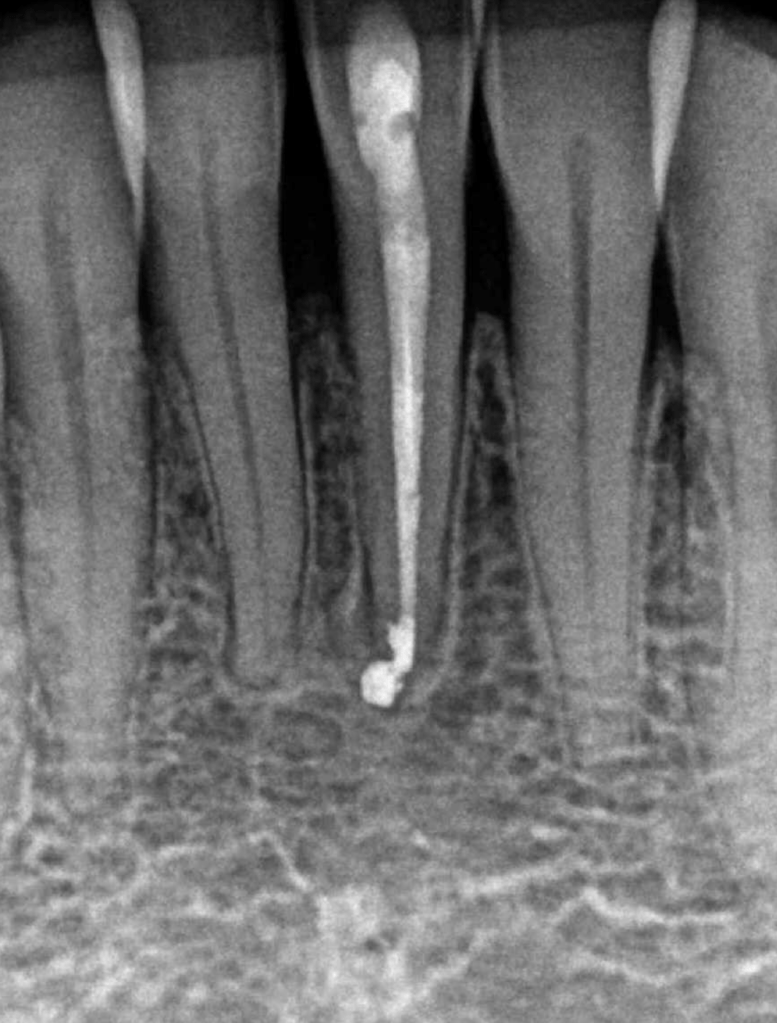

Fistula, dent in dente